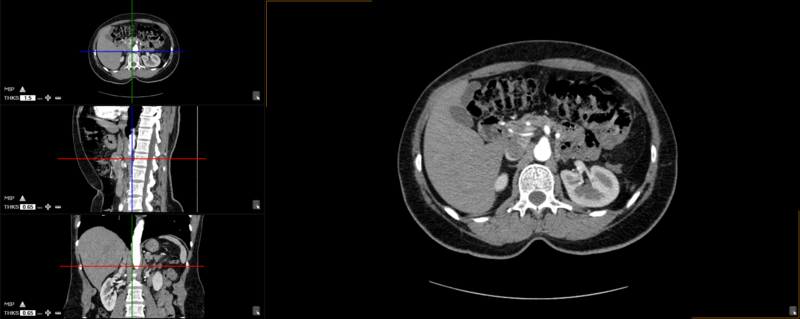

The user can choose from any of these predefined viewing protocols within the MPR mode:

Here are the different viewing protocols you can choose from: